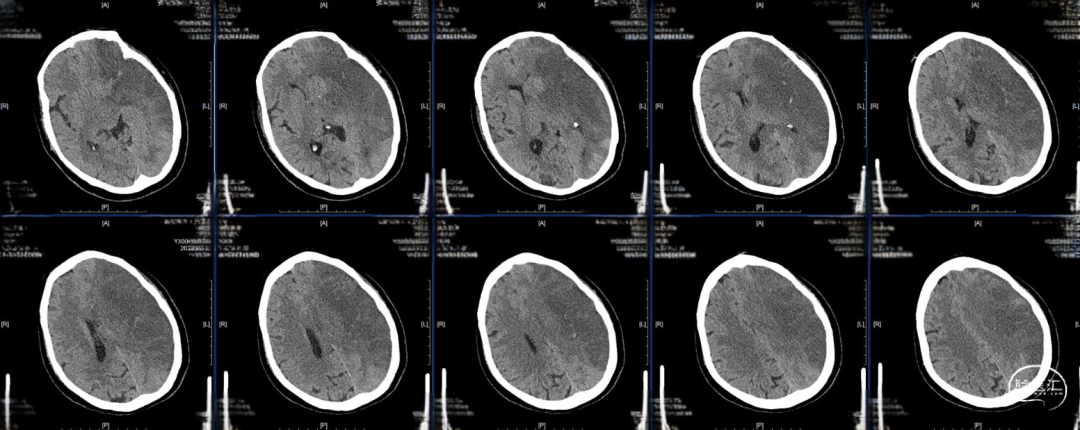

术后24小时复查CT,高灌注、轻肿胀,未见明显出血,轻度镇静至停用镇静,过程中可唤醒,自然复苏,呼吸机维持。

术后48小时复查CT,左半球大片低密度病灶、中线偏移,有主动睁眼、遵嘱动作,暂停呼吸机,延迟拔管,备去骨瓣。

术后96小时复查CT,左侧半球肿胀未继续进展,嗜睡,易唤醒、有睁眼、遵嘱动作,右侧肢体有自主动作,拔除气管插管。

术后第14天启动抗凝,术后第19天复查CT,术后第20天出院,NIHSS评分8分,mRs评分4分。